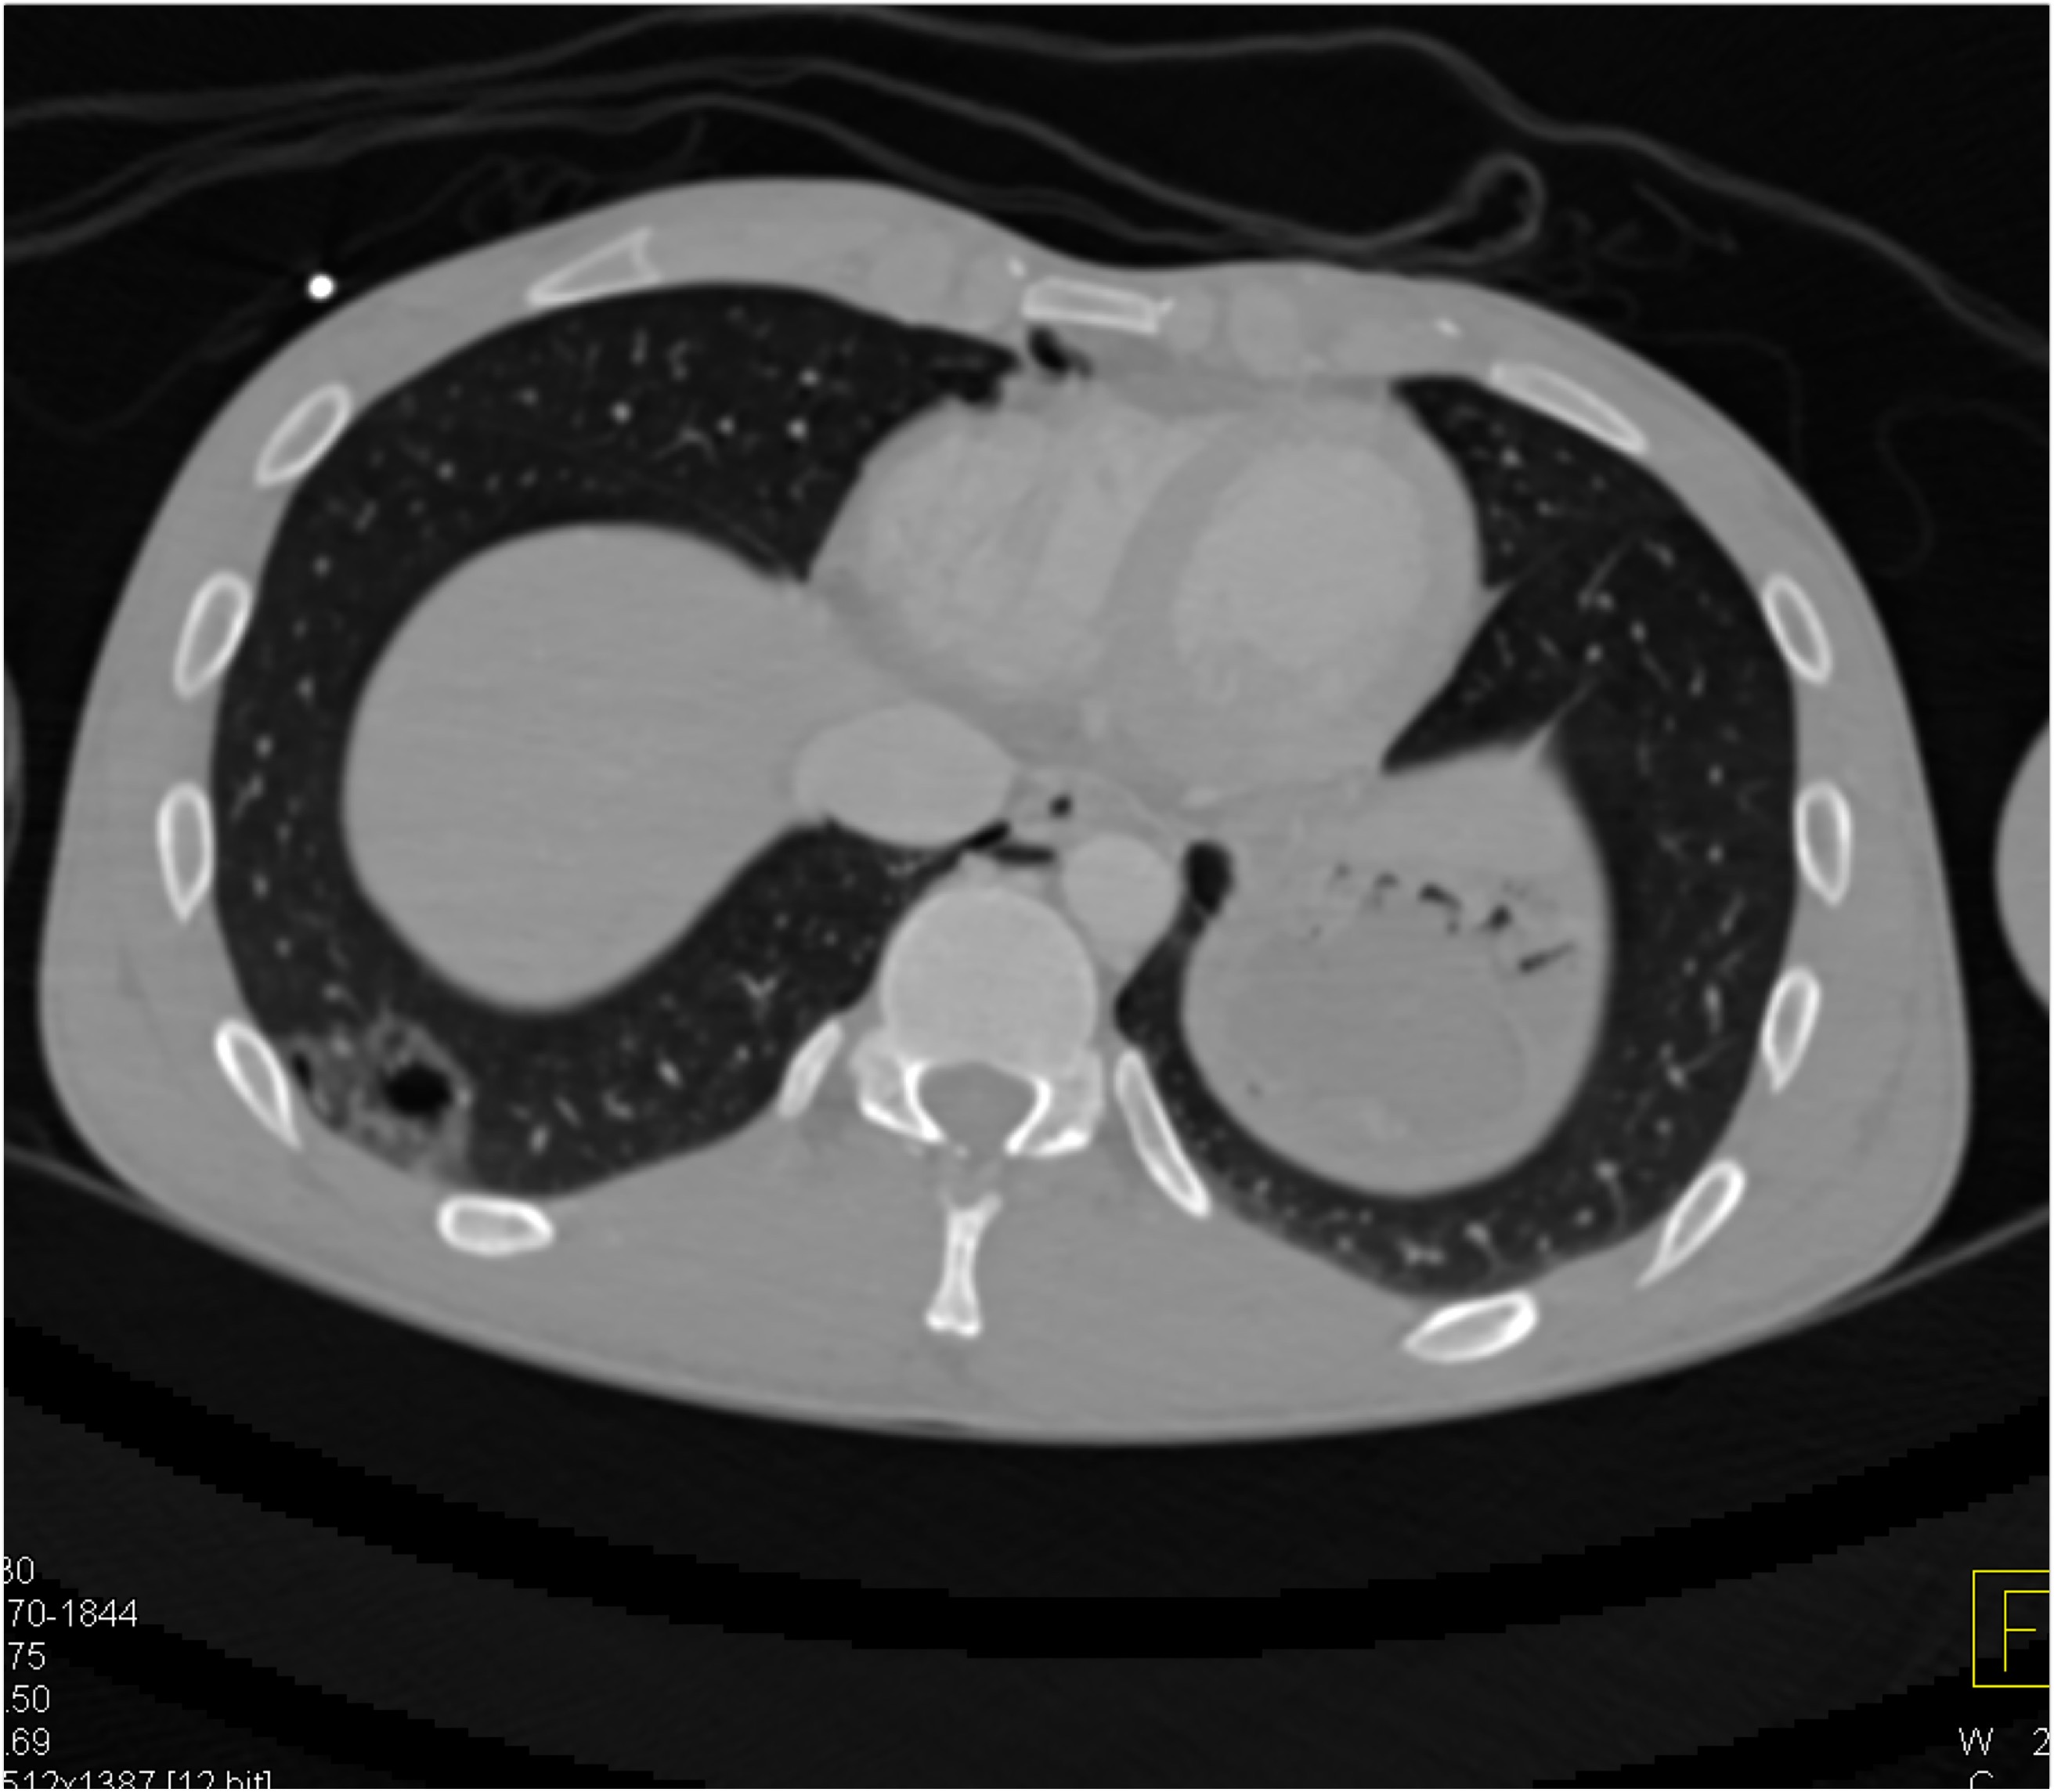

3) The most likely diagnosis in this case is?

lung cancer

lymphoma

pulmonary artery aneurysm

sarcoidosis